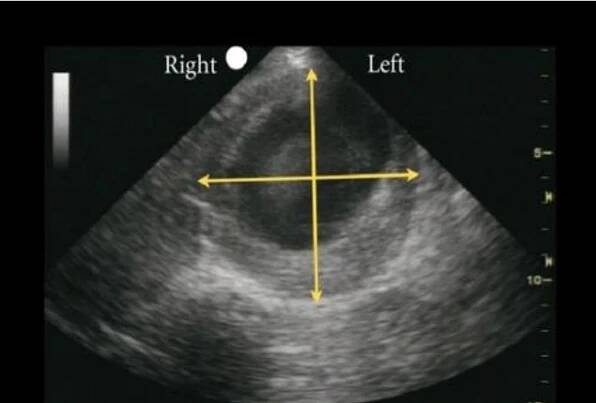

Úvod: Aneuryzma abdominální aorty (AAA) je poměrně častý a závažný stav v cévní chirurgii. Diagnostika, indikační proces a léčebný postup se opírají o guidelines, dle kterých je zákrok indikován při průměru AAA nad 55 mm.